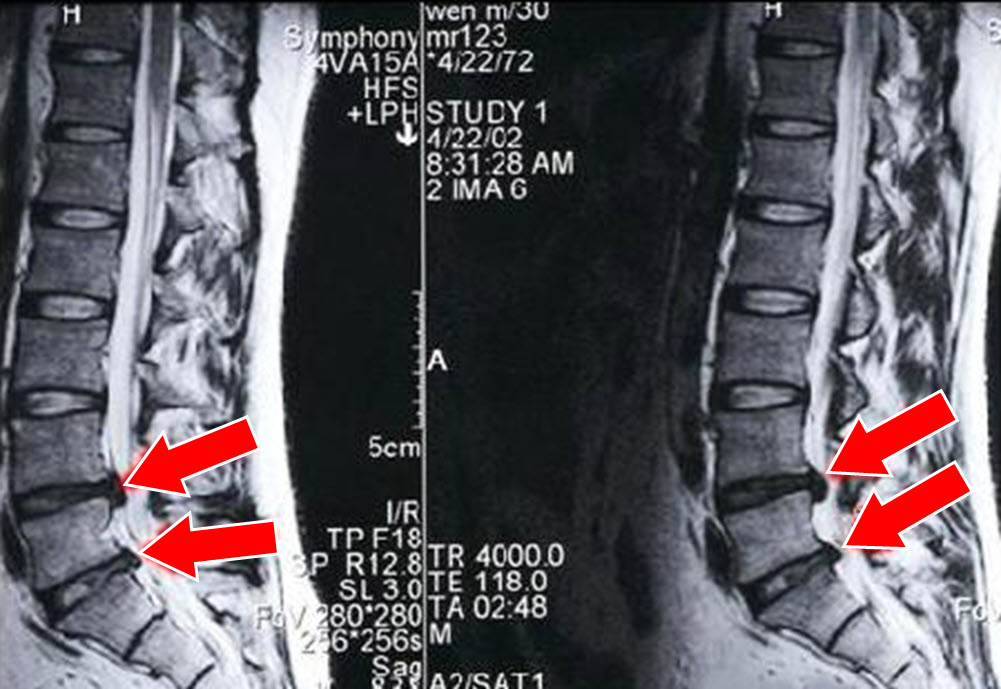

慢性腰痛の原因は、腰部の筋肉が硬直し、腰椎の間隔が狭くなり、その間にあるクッションの椎間板が押し出され(上図矢印の部分)、神経を圧迫することで、足が痺れ、足の感覚異常が出てくるのです。